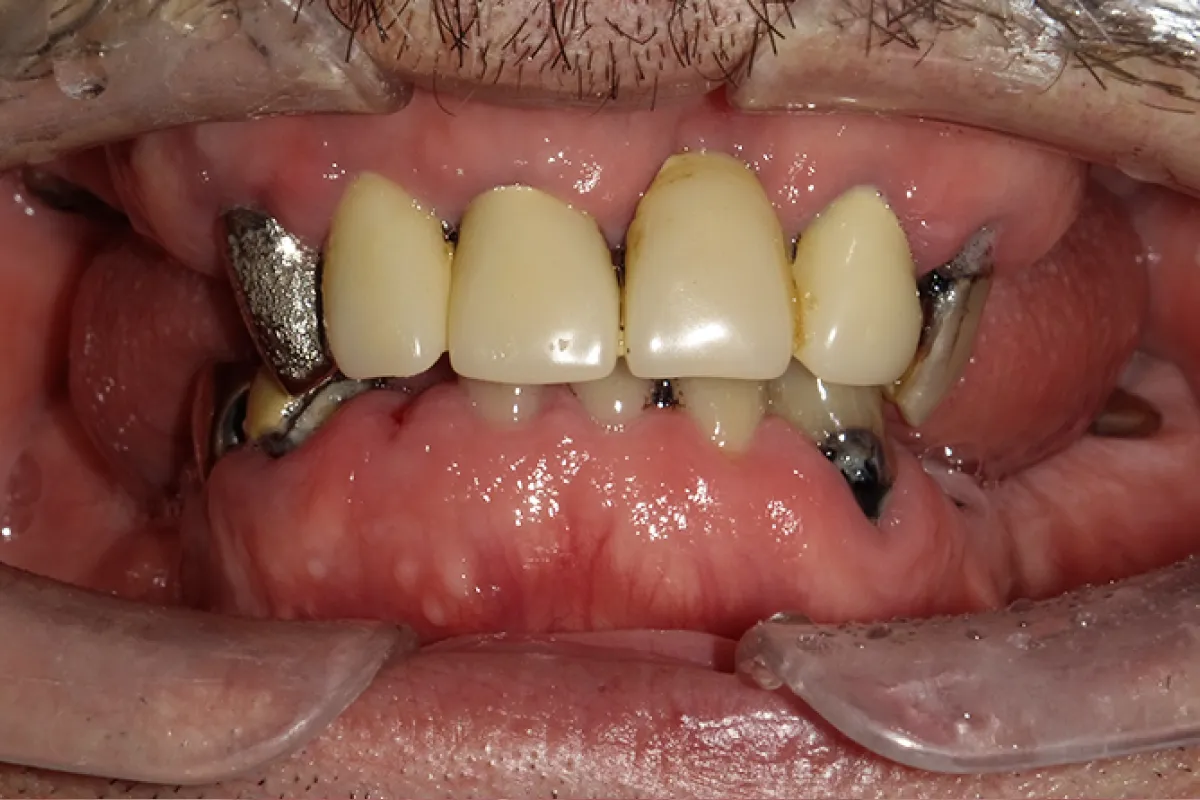

患者様のお悩み 歯牙動揺による咀嚼障害 (欠損や動揺歯が多く噛めない、入れ歯で痛みが出る) 治療概要 インプラント・オールオン4・抜歯・ジルコニア 前歯を含めた複数の部位で歯牙の自然脱落があり、どうにかした […]